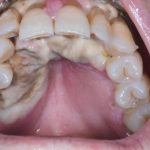

Fig. 11B Caso clinico di mucosite orale indotto dalla assunzione di cis-platino, caratterizzato dalla presenza di ulcerazioni e necrosi tissutale diffusa.